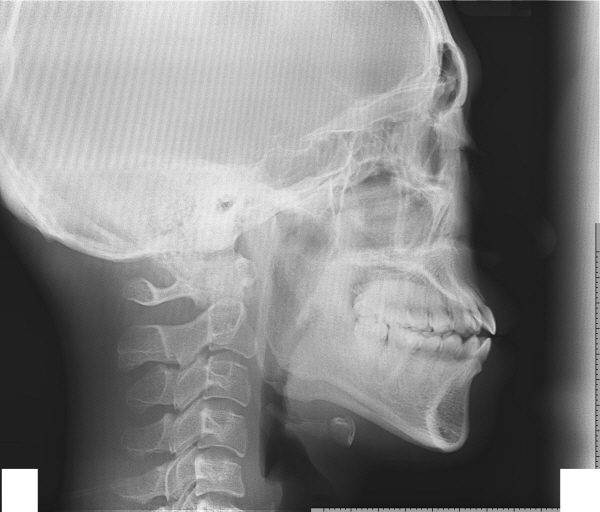

제가 지금 치아교정하는 중인데 엑스레이 사진 상태거든요...

제 경우에 스크류를 심어서 상악과 하악을 최대한 강하게 당겨서 잇몸뼈를 후방으로 이동시킬 수 있을까요??

현제 발치한 상태구요 하악은 턱끝 말구 잇몸뼈만여...꼭 가능했으면 좋겠어요....ㅜㅜ